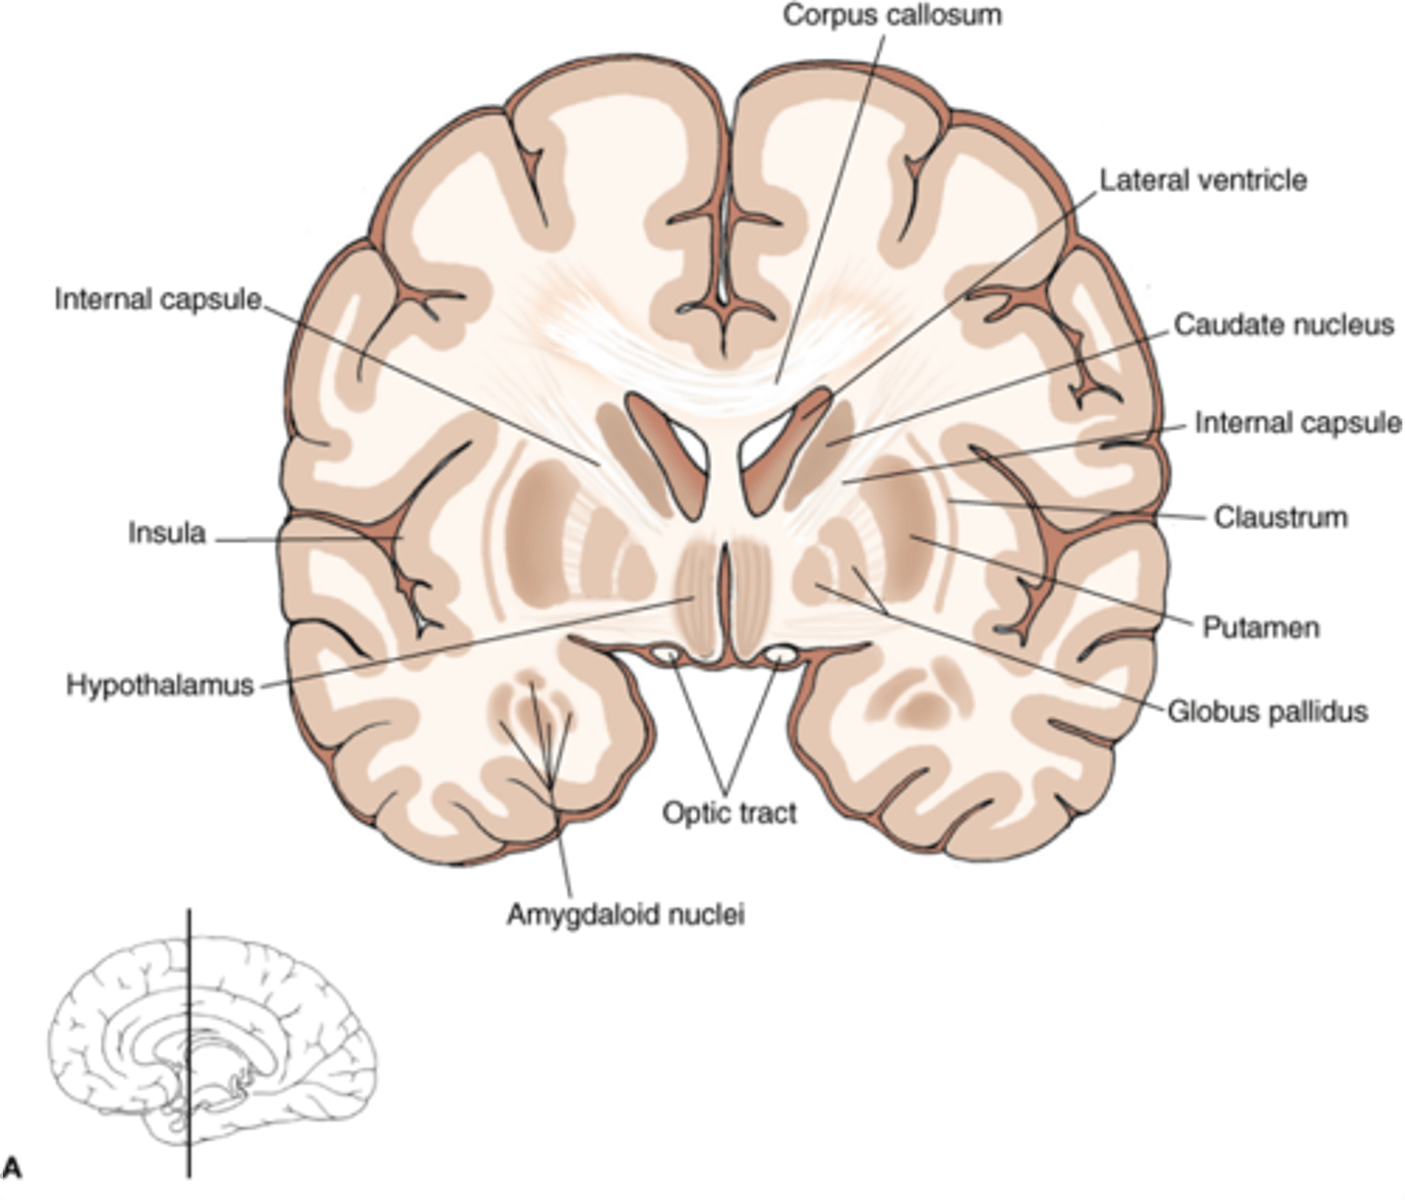

what are 3 key white matter structures found in the cerebrum?

1. corpus callosum

2. corona radiata

3. internal capsule

what cerebral white matter structure is a large bundle of nerve fibers that connects the left and right cerebral hemispheres, allowing them to communicate?

corpus callosum

what is the fan-shaped cerebral white matter sheet that is continuous ventrally with the internal capsule?

corona radiata

what cerebral white matter structure is a tract that carries sensory and motor information to and from the cerebral cortex?

internal capsule

what cerebral white matter structure is found between the basal ganglia?

internal capsule

what are the 3 regions of the internal capsule?

1. anterior limb

2. genu

3. posterior limb

what cerebral gray matter structure is a collection of subcortical nuclei primarily involved in motor control?

basal ganglia

what cerebral gray matter structure has a gate-keeping mechanism for the initiation of motor movement (choosing which actions to allow and which to inhibit)?

basal ganglia

what cerebral gray matter structure has roles in motor learning, executive functions, behaviors, and emotions?

basal ganglia

what are the 3 parts of the basal ganglia? what runs between them?

1. caudate nucleus

2. putamen

3. globus pallidus

internal capsule

what part of the basal ganglia is the C-shaped structure that is most medial?

caudate nucleus

what part of the basal ganglia is medial to the putamen?

globus pallidus

the putamen and globus pallidus of the basal ganglia are collectively called the _______________ nucleus

lentiform